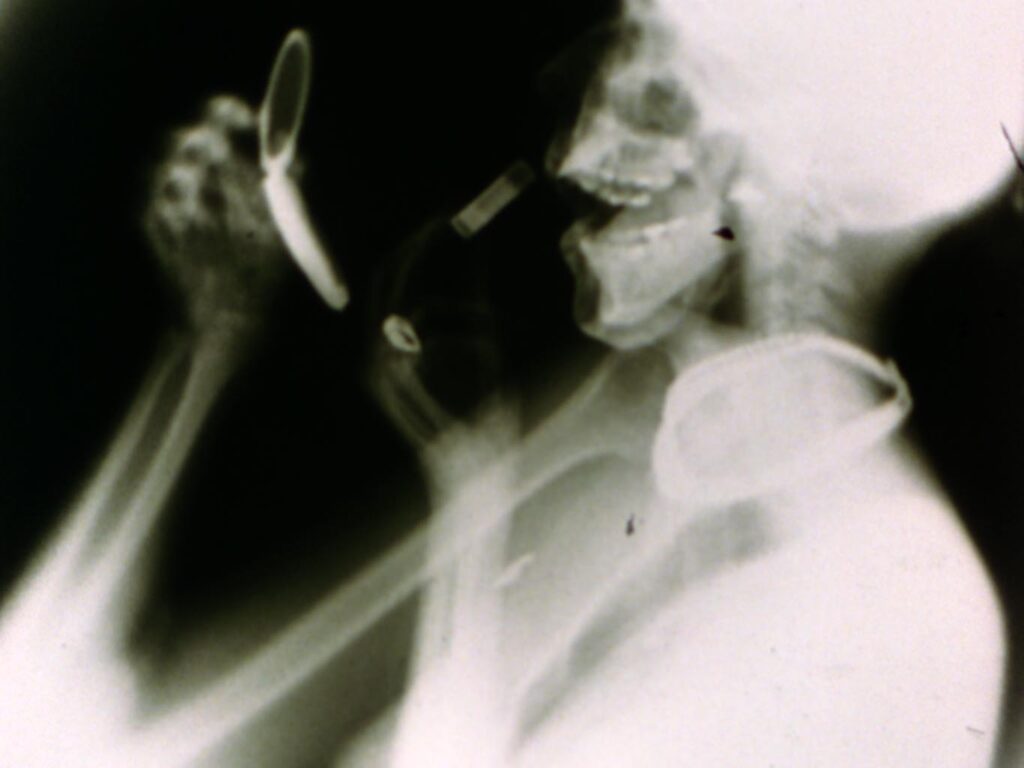

Barbara Hammer, Sanctus (1990)

Barbara Hammer’s film, “Sanctus” (1990) will be included in “X-RAY: The Power of Roentgen Vision” at Weltkulturerbe Völklinger Hütte in Saarland, DE opening on November 9, 2025!

“Sanctus” (1990), film still (courtesy the Estate of Barbara Hammer, Company, KOW, and Electronic Arts Intermix)

"Sanctus" (1990) by Barbara Hammer is now on view at the Art Institute of Chicago!

Barbara Hammer's film, "Sanctus" (1990) will be featured in the exhibition "Overexposed: Art, Technology, and the Body" at the Museum of Moving Image in New York, opening on March 14, 2026!

“Sanctus” (1990) by Barbara Hammer will be featured in “Sexuality Summer School”, a public events program hosted by the University of Manchester at HOME in Manchester, UK!